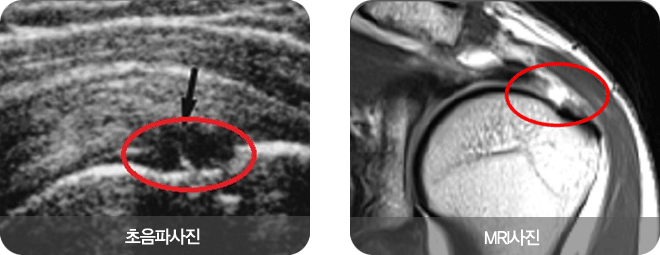

환자의 증상과 진찰을 토대로 먼저 진단하며 엑스레이, 초음파 및 MRI 등의 영상검사를 병행합니다. 파열이 진행할수록 진찰 소견상 파열이 느껴지거나 만져지기도 하며 근 위축이 관찰되기도 합니다. 파열된 근육의 근력을 측정하는 다양한 검사들이 있으며 각각의 힘줄 파열에 대한 검사법을 시행합니다. 현재 널리 사용되고 있는 영상검사는 초음파와 MRI입니다. 회전근개 파열 유무뿐 아니라 파열의 크기, 정도 및 파열된 건 끝부분의 퇴축정도를 알 수 있어 수술 방법을 선택하고 계획하는데 도움이 됩니다. |